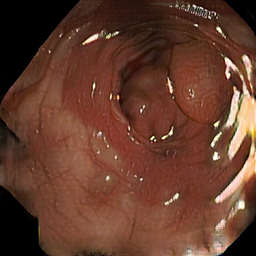

Test data: Kvasir-SEG

• 1000 images

• various sizes

• Each image contains 1 polyp

• Collected and annotated by medical professionals

Jha, Debesh, et al. "Kvasir-seg: A segmented polyp dataset." MultiMedia modeling: 26th international conference, MMM 2020, Daejeon, South Korea, January 5–8, 2020, proceedings, part II 26. Springer International Publishing, 2020.